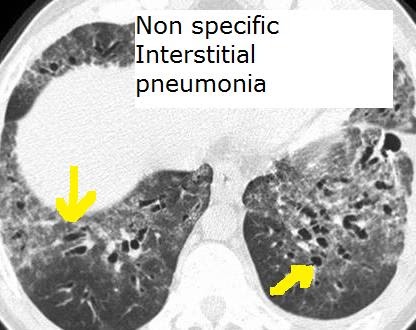

Non specific view

Non specific view 110 фотографий